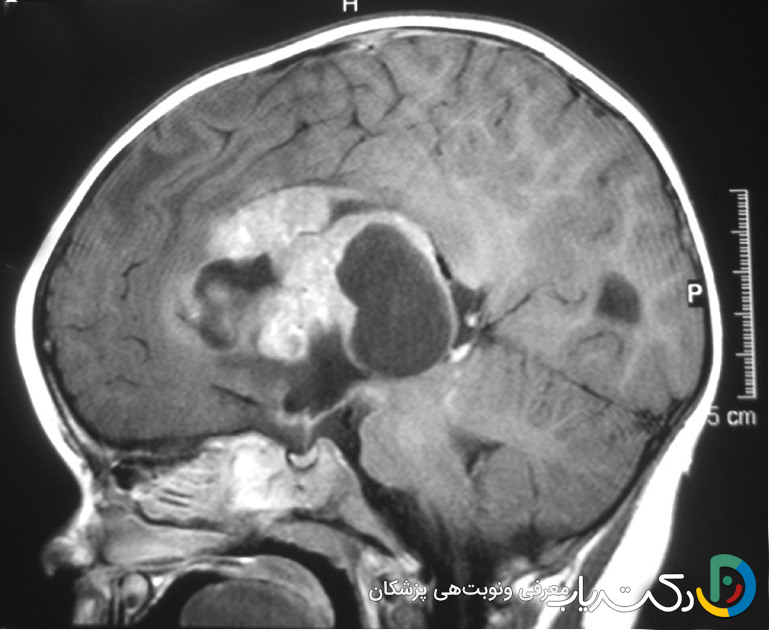

- MRI (تصویربرداری تشدید مغناطیسی): این روش به دلیل نمایش جزئیات دقیق بافت نرم مغز، استاندارد طلایی برای تشخیص تومور مغزی است. سکانسهای مختلفی از MRI وجود دارد؛ مثلاً MRI با تزریق ماده حاجب (گادولینیوم) باعث درخشان شدن تومورهایی میشود که سد خونی-مغزی را تخریب کردهاند.